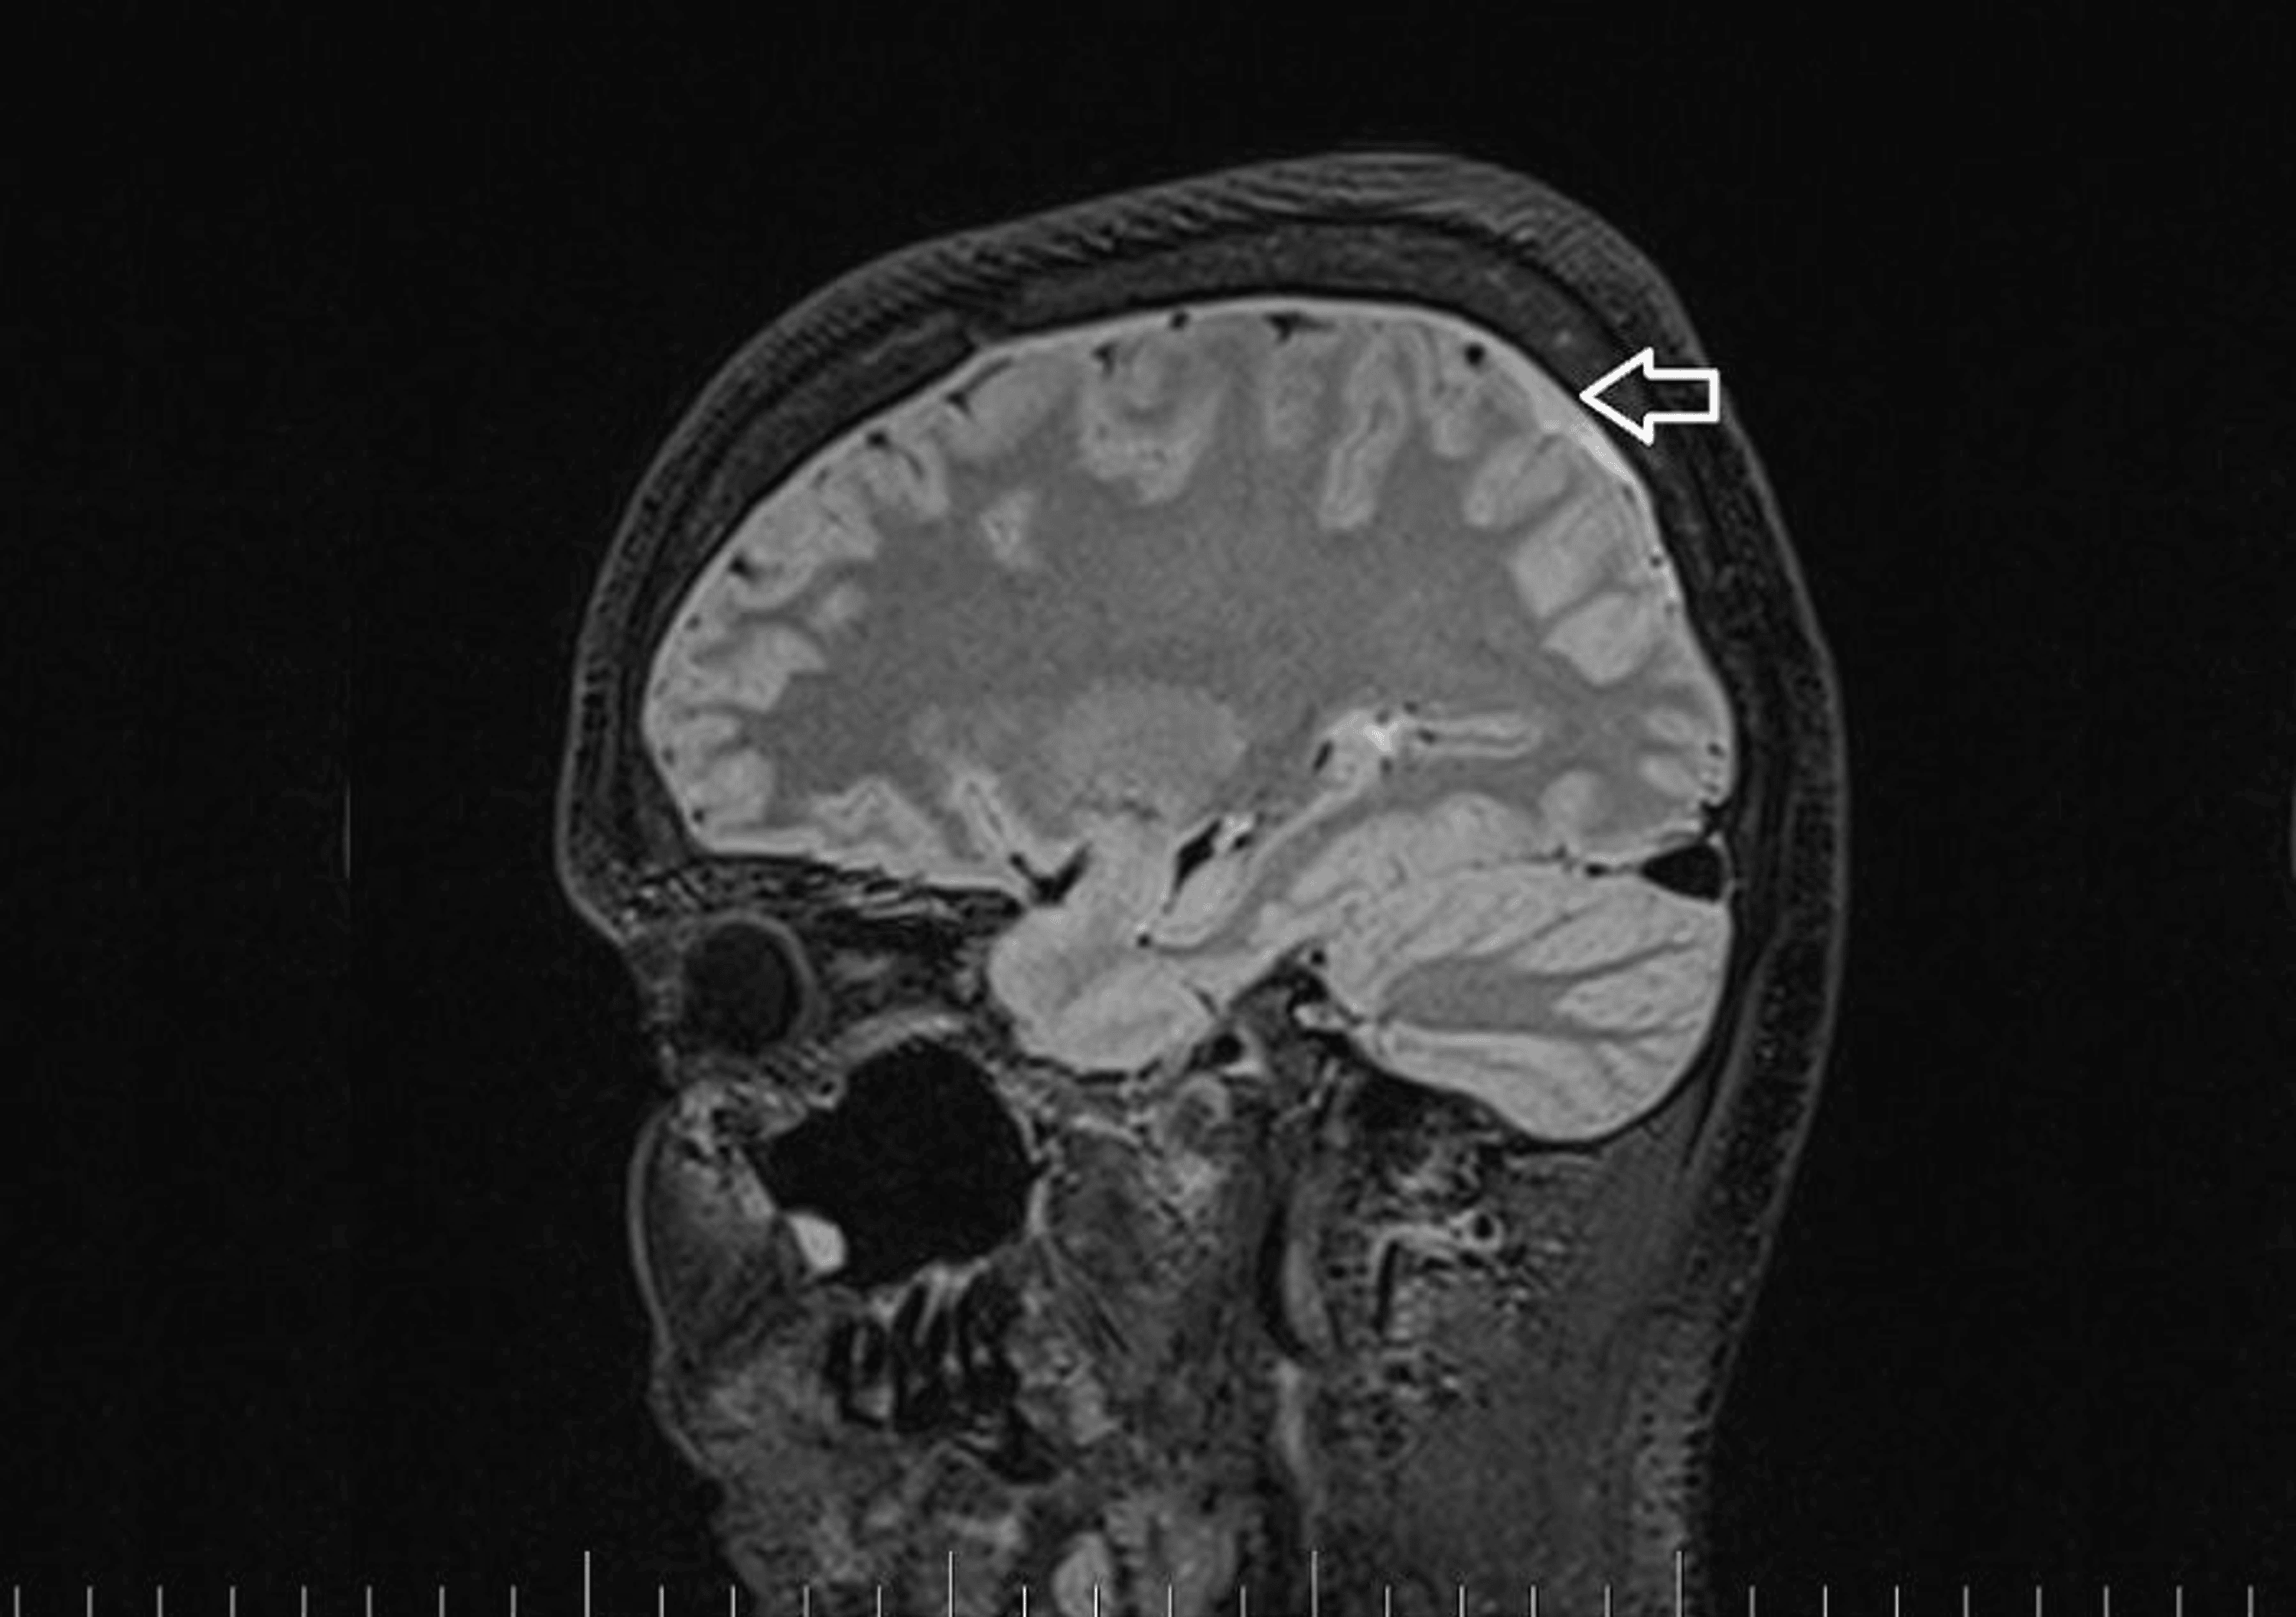

As part of the differential diagnosis, further imaging was performed. A brain MRI on February 1, 2023 (Figure 1) showed the following signs of SIH: subdural fluid collection up to 5.00 mm in the parietal area; diffuse, smooth dural thickening and pachymeningeal contrast enhancement; slightly homogeneous enlargement of the pituitary; cerebellar tonsillar descent into the foramen magnum; distension of the cerebral venous sinuses without thrombosis; and reduced fluid volume in the optic nerve sheath.